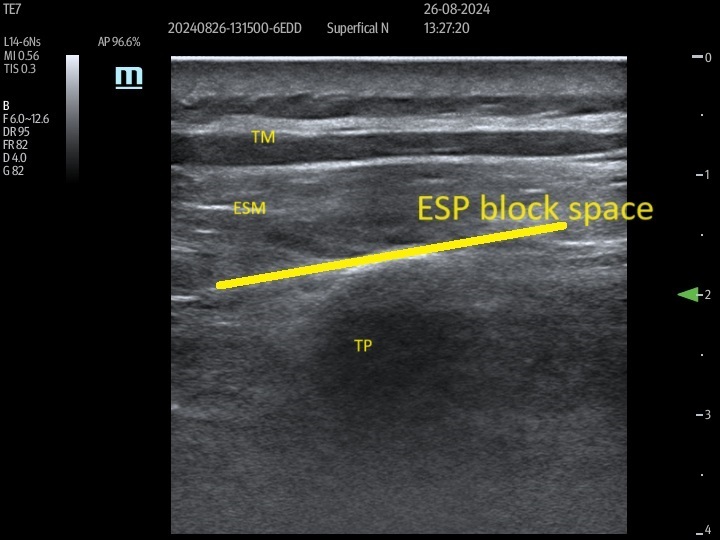

The ESP block was performed with the patient in a sitting position. After skin disinfection, a linear high-frequency (L14–6NS) ultrasound probe (Mindray, UMT-400, Mindray Building, Keji 12th Road South, High-Tech Industrial Park, Nanshan, Shenzhen, People’s Republic of China), covered with a sterile sheath, was positioned sagittally 1–2 cm lateral to the midline at the level of the ninth thoracic vertebra (T9). The T9 level was earlier identified by palpating the spinous process of the seventh cervical vertebra and counting down nine intervertebral spaces. After identifying the erector spinae muscle (ESM) and transverse process, a 21-gauge needle (Echoplex+ REF 6194.853 85 mm) was inserted deep into the ESM in a cranio-caudal direction, using an in-plane technique (Figure 1). The needle was advanced, ensuring that it crossed all muscle layers until it contacted the transverse process. Correct needle placement was confirmed by administering 0.5–1 mL of local anesthetic. After ensuring negative aspiration for blood, 30 ml of 0.35% ropivacaine was injected slowly deep into the ESM. This procedure was performed bilaterally on each patient.

FIGURE 1

Erector spinae plane (ESP) block block as seen on ultra-sound examination. Para sagittal ultrasound view at the T9 level in a slightly more medial plane prior to ESP block showing trapezius muscle and erector spinae muscle. The line shows the target site of the block. TM – trapezius muscle, ESM – erector spinae muscle, TP – transverse process